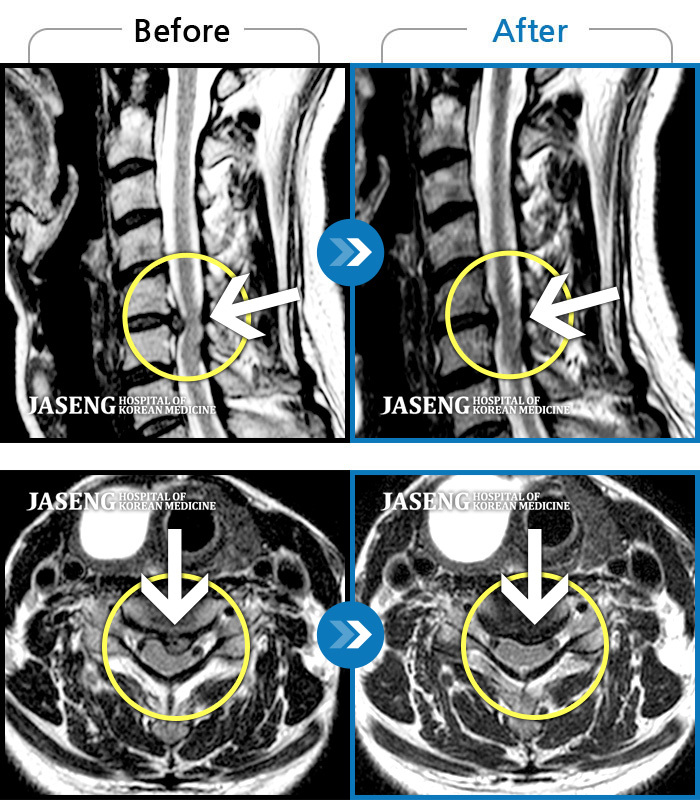

[뱸] 19.11.28~25.05.06

ȯںп Ǹ ǿ ԿǾ, ο ġ ۿ Ƿ ġḦ Ͻñ ٶϴ.